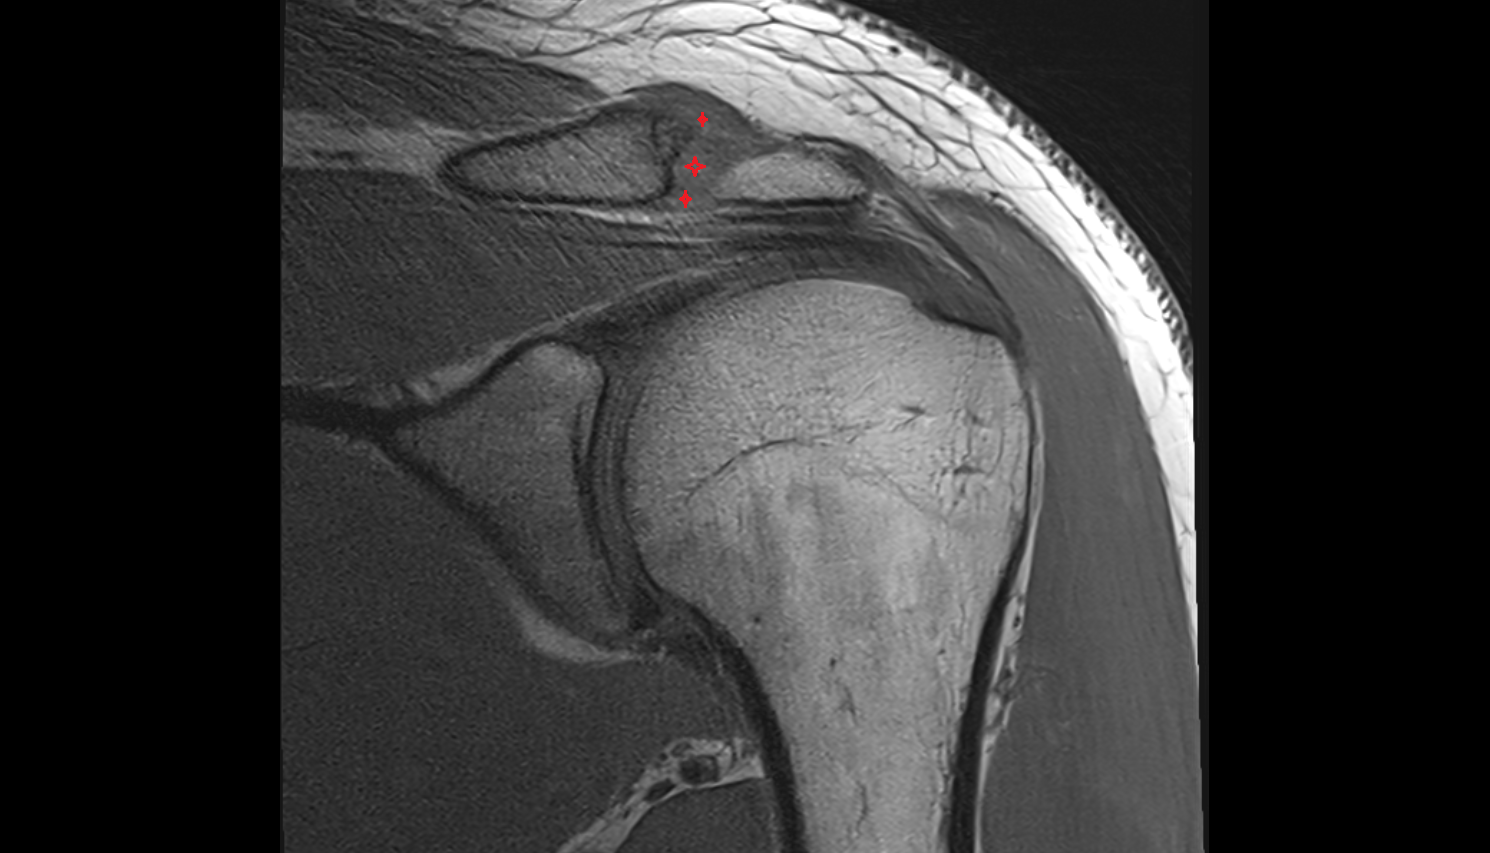

- Supraspinatus tendon

- Shoulder joint (glenohumeral joint)

- Subacromial space

- Glenoid labrum